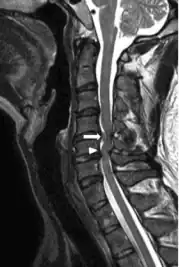

Image indicates C5–C6 with severe spinal cord compression (and large disc herniation at C4–C5 )

Compressive myelopathy at the C6-C7 level due to disc protrussion